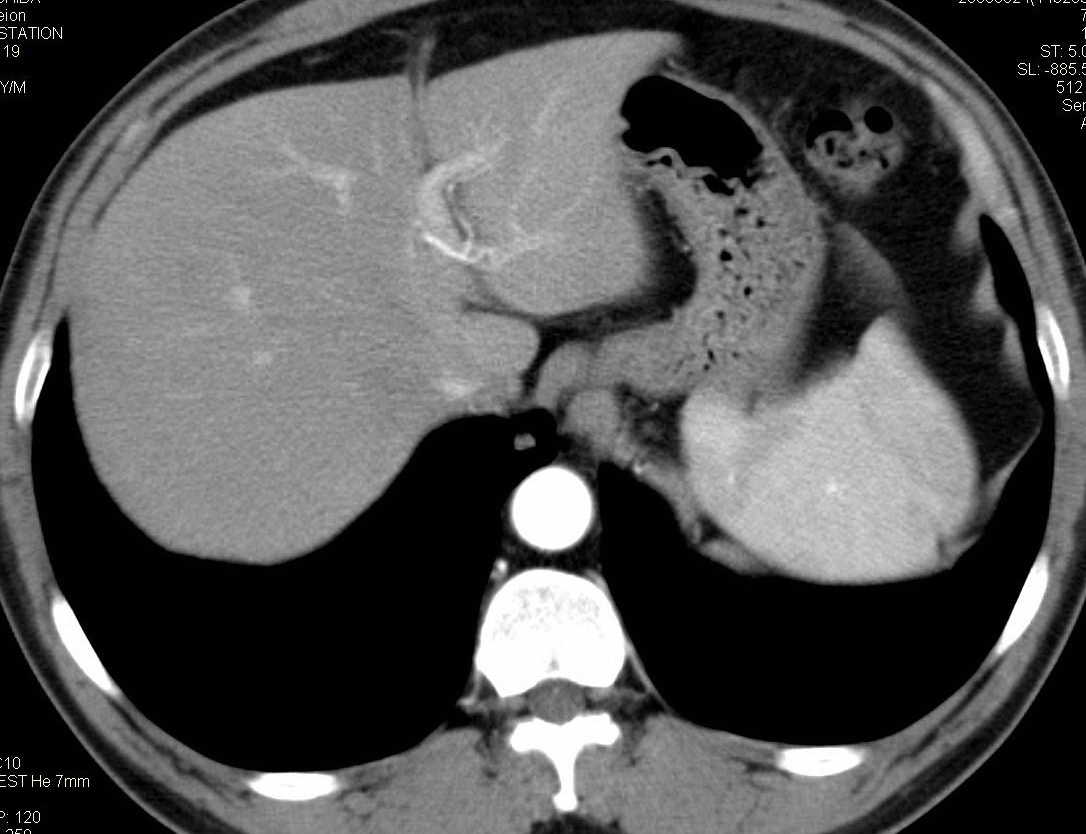

标题: CT15857:男性 58岁 咳痰带血 无发热 请各位大侠发表一下意见 [打印本页]

标题: CT15857:男性 58岁 咳痰带血 无发热 请各位大侠发表一下意见

两肺下叶肺纹理增多、增粗并呈“树芽状”改变。支气管扩张呈囊状,部分呈柱状改变。其周围可见散在的斑片样及条索样密度增高影,右肺下叶近叶间胸膜可见一形态不规则的高密度结节影,并与胸膜粘连。

考虑:支扩并发感染。

双肺多发炎性病灶,结核可能性大,建议抗炎治疗复查.右肺下叶前基底段结节灶,高度警惕肺癌可能

双肺间质性改变(间质纤维化?)伴支扩。右肺下叶有毛刺的小结节,考虑周围型肺癌可能性。